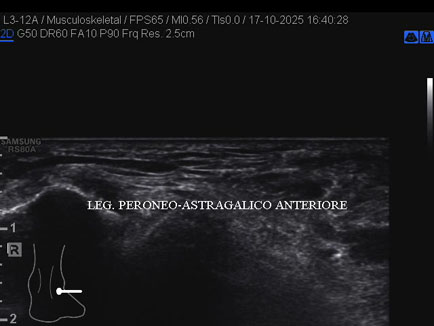

Ecografia del: 17/10/2025

Età Paziente: M

Commento all'esame: rottura del fascio antero-superiore del legamento fibulo-talare anteriore con integrità del fascio postero-inferiore in giovane calciatore.

Conclusioni: rottura del fascio antero-superiore del legamento fibulo-talare anteriore destro (tear of the anterosuperior bundle of the right anterior talofibular ligament).